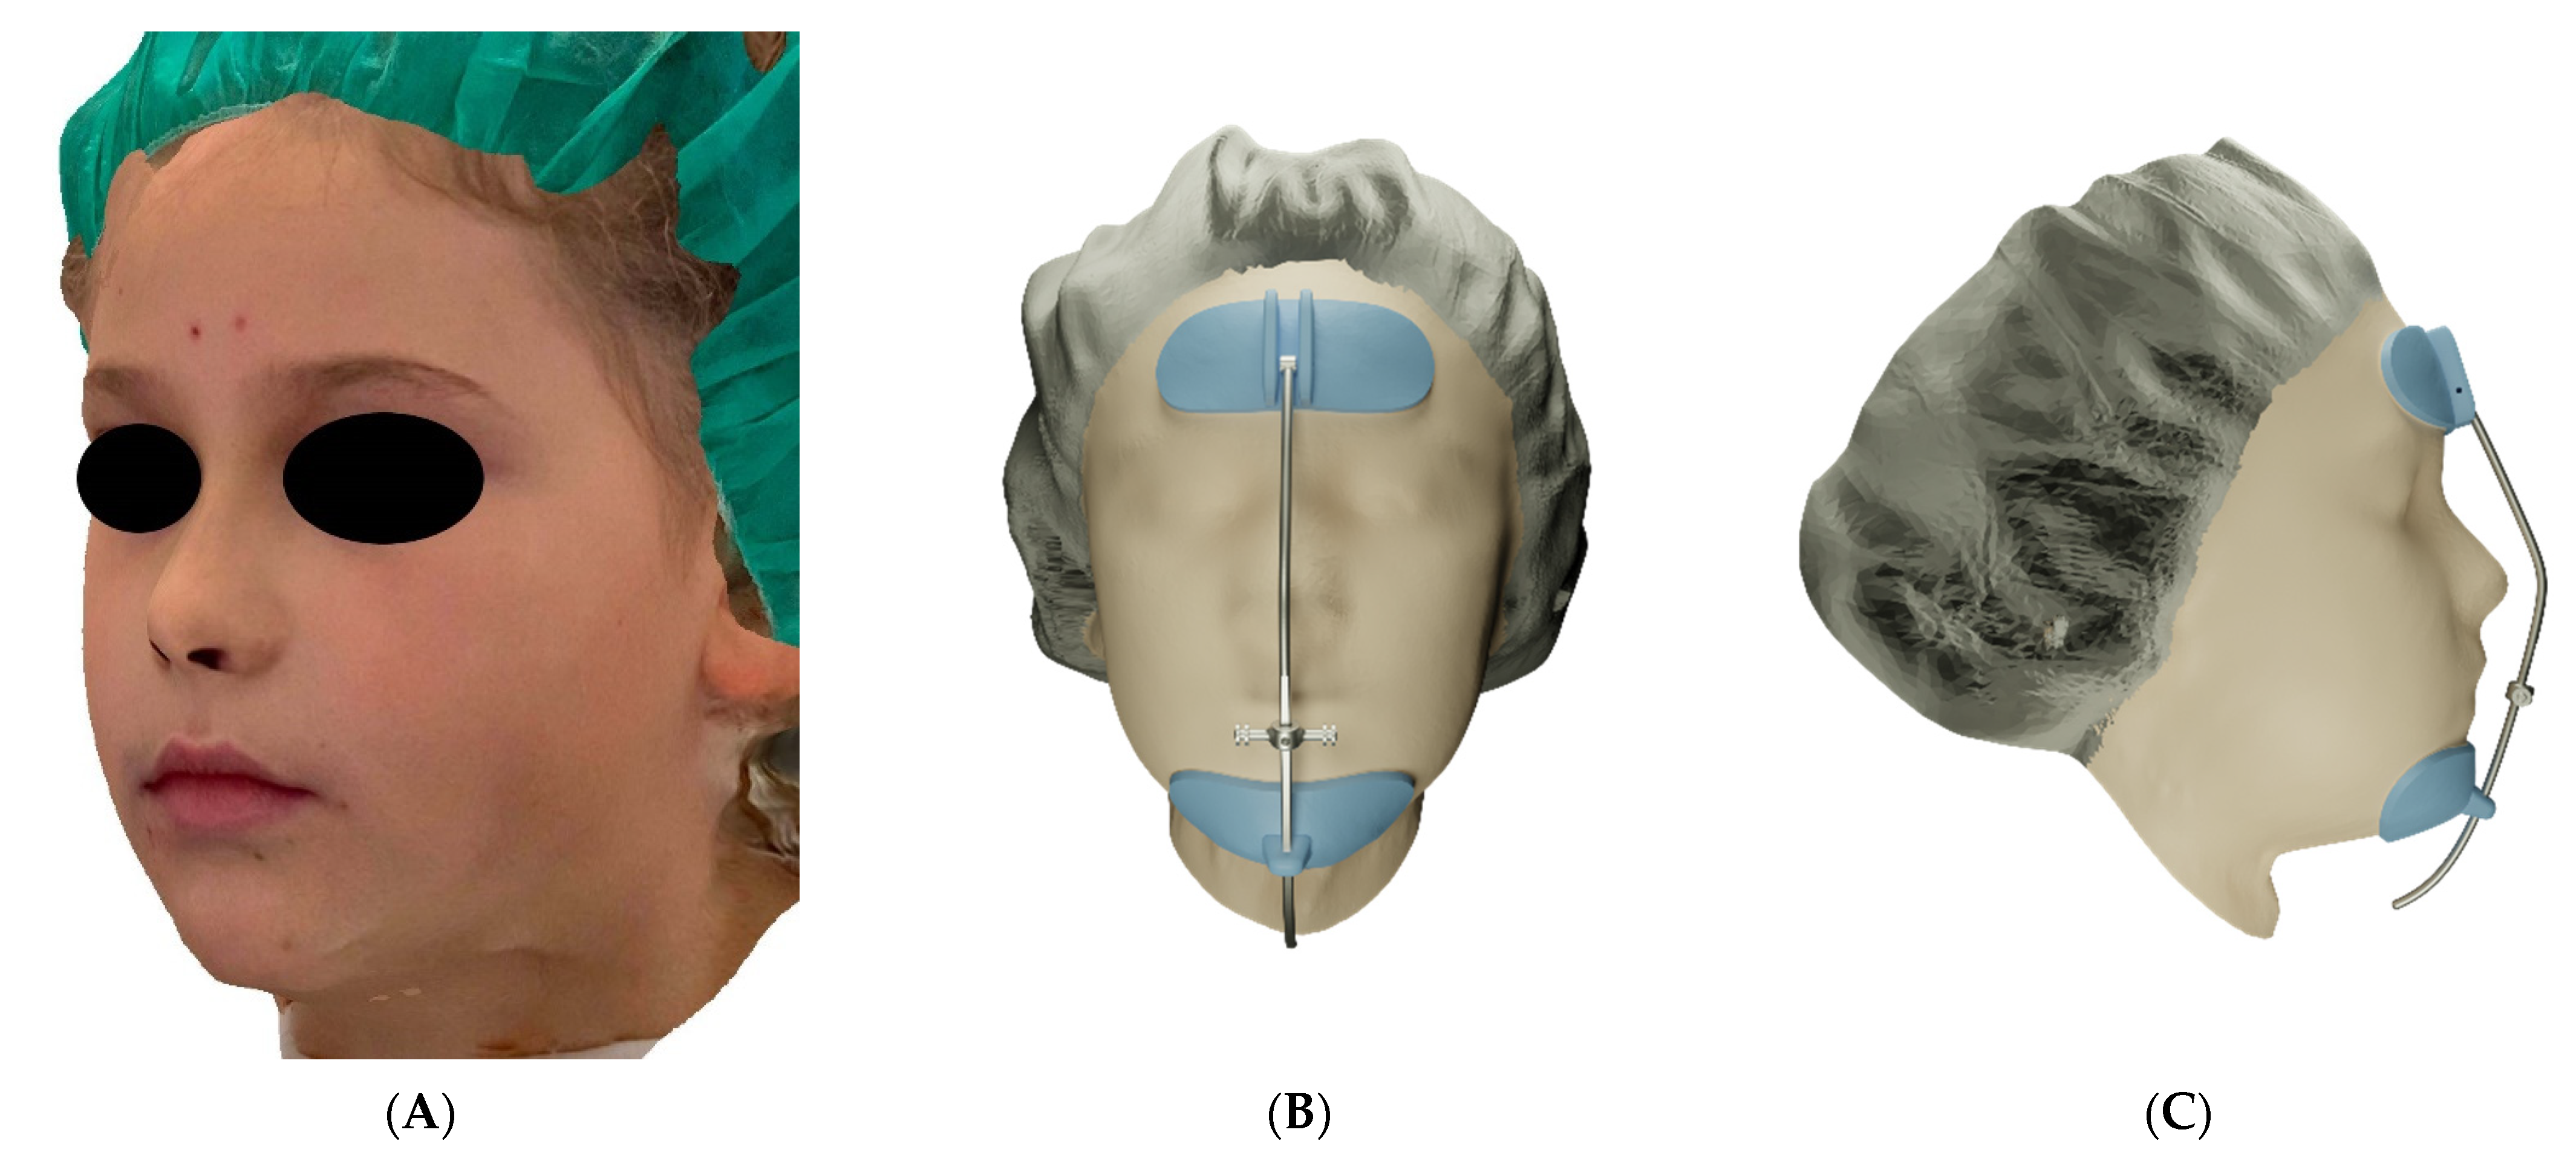

2. Materials and Methods

3. Results